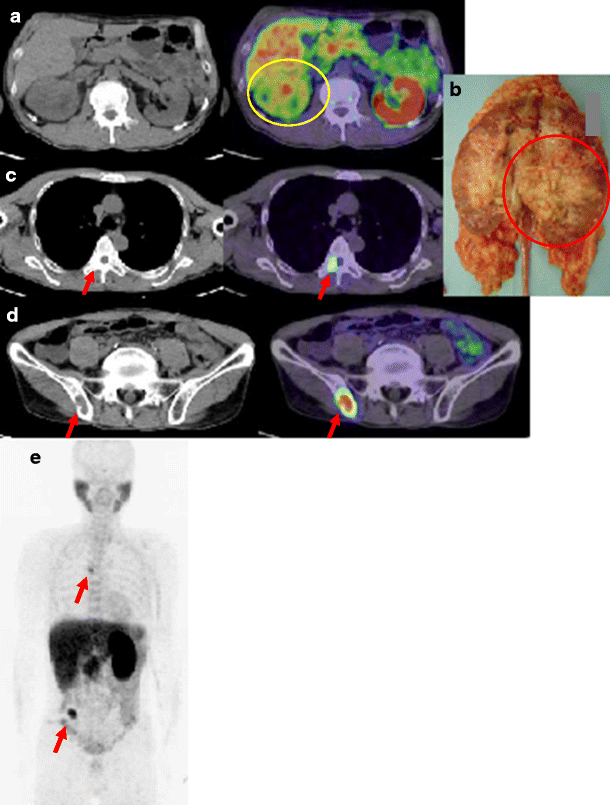

Urothelial carcinoma of the right renal pelvis in patient 12. a Choline PET/CT images of the primary tumour at 10 min after injection (SUVmax 7.85). b Photograph of the primary tumour after resection. Circles tumour sites. c, d Choline PET/CT images of the metastatic lesions at the 12th thoracic spine (SUVmax 7.36, c) and the right iliac bone (SUVmax 10.39, d) at 10 min after injection. Arrows bone metastases. e Maximum intensity projection image. The metastatic lesions in the sixth thoracic spine and the right iliac bone are seen (arrows)